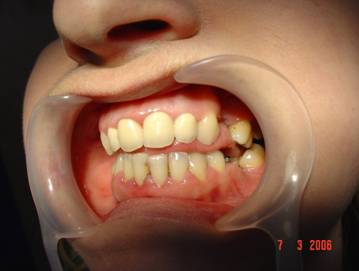

Cazul 2: L.A., fem:

Initial clinic si radiologic se observa prezenta resturilor radiculare frontale superioare.

Cazul dupa restaurarea functiei fizionomice.